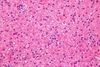

Milchglashepatozyt

Hepatozyt mit aufgetriebenem, transparentem Zytoplasma. Entsteht durch Hyperplasie des endoplasmatischen Retikulums, das wiederum durch eine gesteigerte Produktion des viralen Hüllmaterials (HBs-Antigen) bedingt ist HEPATITIS